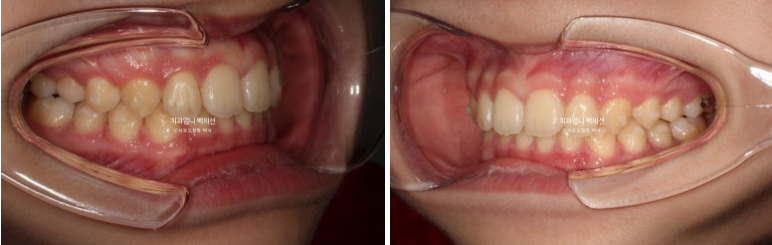

24.09

앞니 돌출은 해결이 되었으나 앞니가 깊게 물리는 과개교합이 남아있습니다.

악궁모양은 예뻐졌습니다.

과개교합을 좀 더 개선하고자 재제작에 들어갑니다.